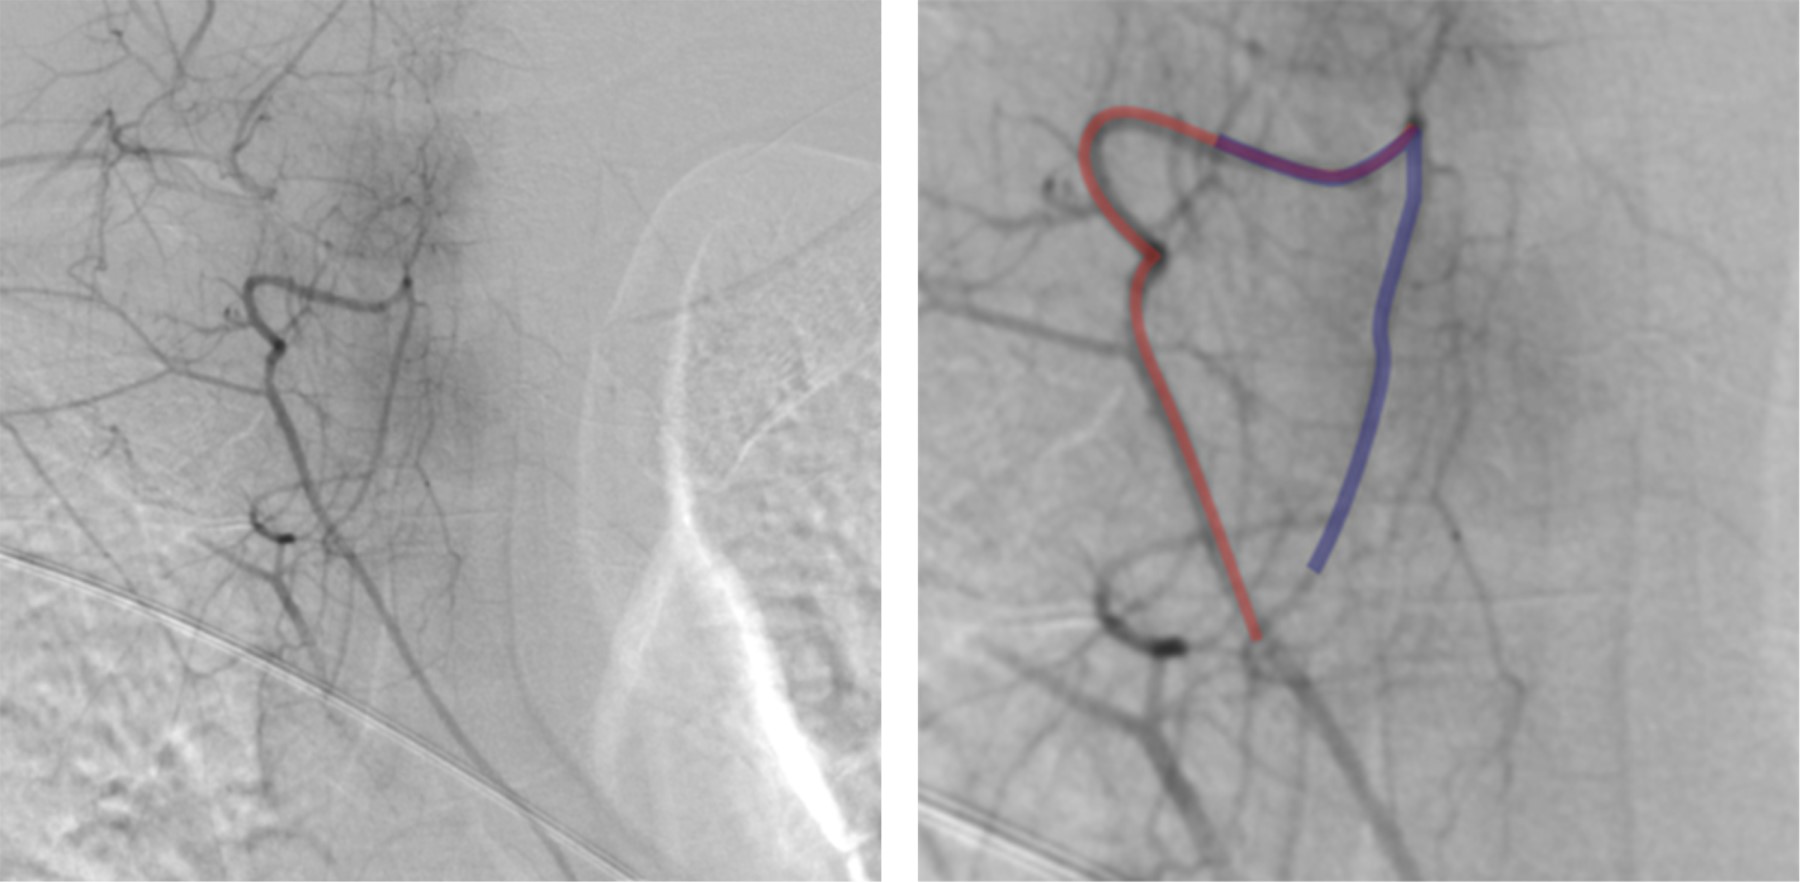

En la angiografía espinal diagnóstica en sala de hemodinamia, se llevó a cabo la canalización de la arteria femoral. Se logró identificar el sitio de la fístula arteriovenosa dural espinal a nivel de T5 (Figura 2).

Figura 2